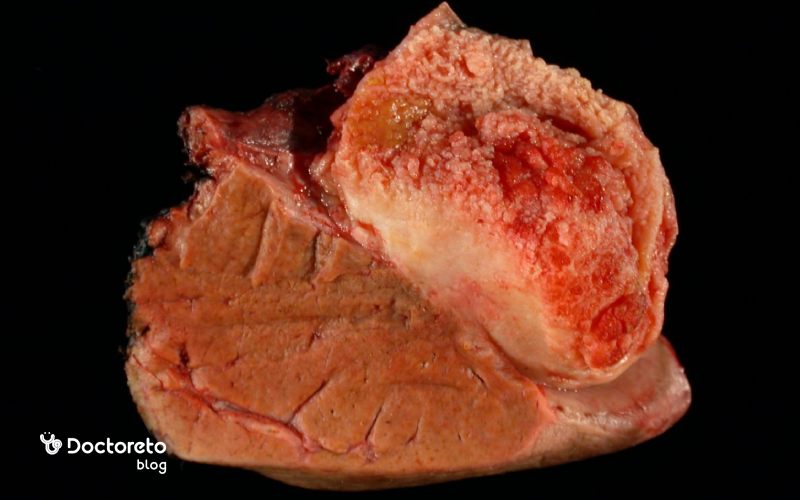

سرطان کیسه صفرا نوعی بیماری سرطانی است که در آن سلولهای پوشانندهٔ داخل کیسه صفرا دچار رشد غیرطبیعی و کنترلنشده میشوند. در بیشتر موارد، این سرطان از نوع آدنوکارسینوم است، یعنی از سلولهایی که وظیفهٔ ترشح و پوشاندن دیوارهٔ داخلی کیسه صفرا را دارند منشاء میگیرد. سرطان کیسه صفرا در مقایسه با سایر سرطانهای دستگاه گوارش نادر است، اما مشکل اصلی آن تشخیص دیرهنگام است. زیرا در مراحل اولیه علائم مشخصی ندارد و معمولاً آن را با بیماریهای شایعتری مانند سنگ کیسه صفرا یا التهاب کیسه صفرا اشتباه میگیرند.

سرطان کیسه صفرا بیشتر بر اساس نوع سلولی که منشاء تومور است دستهبندی میشود. حدود ۹۰ درصد موارد از نوع آدنوکارسینوم هستند که از سلولهای غدهای مخاط داخلی کیسه صفرا شروع میشود. برخی از این سرطانها رشد آهستهتری دارند و بعضی دیگر تهاجمیتر هستند. آشنایی با انواع سرطان به پزشک کمک میکند تا روش درمانی مناسبتر را انتخاب کند.

- آدنوکارسینوم: شایعترین نوع سرطان کیسه صفرا که از سلولهای غدهای شروع میشود.